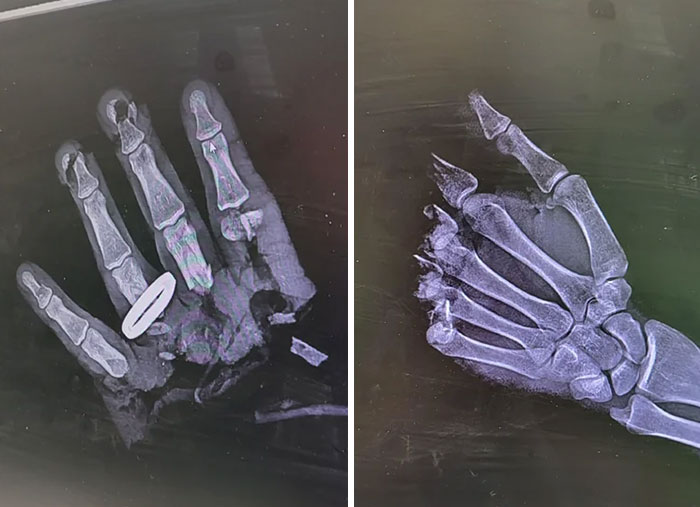

#15 Chainsaw Accident On X-Ray

Image credits: Unusualway